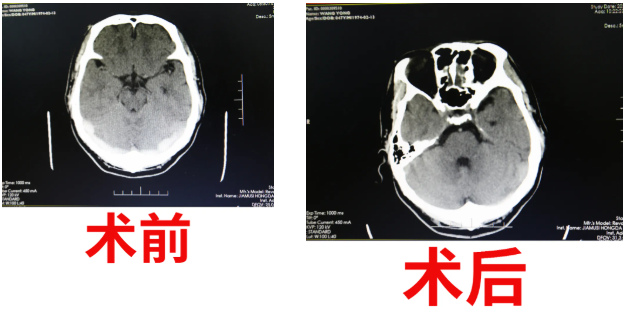

盡管醫(yī)生們穿著沉重的鉛衣奮戰(zhàn),但看到患者的顱內(nèi)靜脈竇血管成功開通的那一瞬間,在場醫(yī)護(hù)人員滿滿的喜悅充斥著手術(shù)室每個(gè)角落。細(xì)節(jié)決定成敗,艾主任準(zhǔn)確把握適應(yīng)癥、術(shù)前縝密計(jì)劃、術(shù)中謹(jǐn)慎操作,介入室護(hù)士嚴(yán)密監(jiān)護(hù),麻醉師的精湛技術(shù),手術(shù)團(tuán)隊(duì)完美配合,在2小時(shí)內(nèi)“生命之流”就被重新開通,王先生順利轉(zhuǎn)回普通病房。

術(shù)后給與患者抗凝、改善循環(huán)等對癥治療。在腦血管病介入科醫(yī)護(hù)人員的精心治療及護(hù)理下,第二日頭痛癥狀完全消失,復(fù)查頭部核磁MRV提示靜脈竇通暢,患者凝血等檢驗(yàn)項(xiàng)目比值逐漸恢復(fù)正常值?;颊呒覍傧矘O而泣,拉住艾主任的手激動(dòng)說道:“我們真是撿回了一條命,沒想到能恢復(fù)這么好,感謝佳木斯大學(xué)宏大醫(yī)院腦血管病介入團(tuán)隊(duì),給了我丈夫新生,也給了我們?nèi)胰诵律南M?,要不以后的日子我們真不知道怎么過了!”。這一幕,作為醫(yī)務(wù)工作者,內(nèi)心都會(huì)感到無比的喜悅,這是手術(shù)成功后的喜悅,也是為生命得以延續(xù)而喜悅。